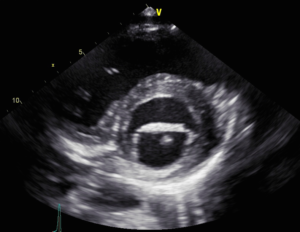

- Trans-esophageal echo [Fig 2,3] showed a mobile mass on the mitral valve. EF was 66% with normal LV function.